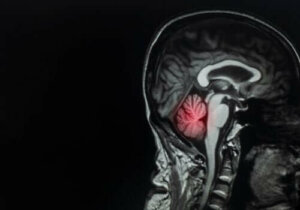

Kreftspredning til hjernen, eller hjernemetastaser, er den hyppigste typen hjernesvulster, og de er en utfordring for leger over hele verden. Faktisk utgjør de omtrent 90% av de totale tilfellene av hjernesvulst.

I den forbindelse er det interessant å merke seg at fordelingen av hjernemetastaser er proporsjonal med blodstrømmen i det aktuelle området. Den er lokalisert i henhold til følgende prosenter:

- 80% av lesjonene i hjernen

- 15% i lillehjernen

- 5% i hjernestammen